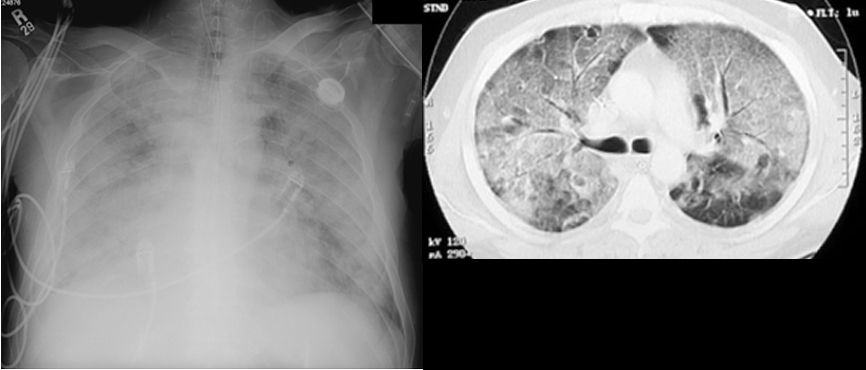

ARDS65 year old male who received induction chemotherapy for AML developed hypoxemic respiratory failure and was intubated. His PaO2 while receiving 100% oxygen was 55. An echocardiogram was normal. CT shows bilateral diffuse ground glass infiltrates. |